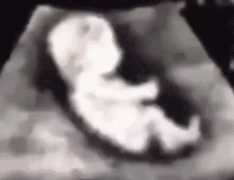

从受精到一个婴儿的诞生,很多人都会觉得孕育一个生命是一个很神奇的过程,也很好奇胎儿是怎么在母体里生长变化的,今天小编就带大家看看从受孕到分娩,胎儿发育的整个过程。...

目前医学上有多种D数的超音波类型,究竟有什么差异性呢?对于产科医生来说,超音波就如同其第三只眼,透过超音波的检测,医师与准爸妈都可以更清楚母体与宝宝生长的健康情形。...